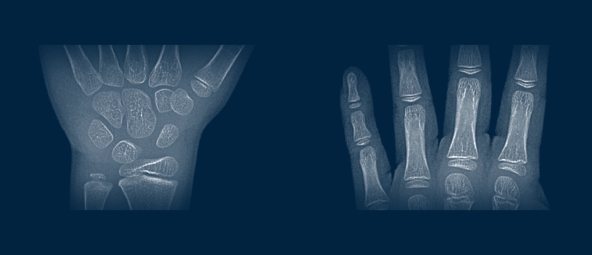

만약 성장기를 통해서도 아이의 키가 생각처럼 크지 않고 있다면 골 연령 측정 검사를 통해 아이의

뼈 나이를 예측하고, 체형 등을 분석하여 성장을 저해시키는 요소를 파악하는 것도 도움이 될 수 있습니다.

성장판은 뼈의 끝 부분에 있는 연골 조직입니다. 어깨, 팔꿈치, 손목, 손가락, 척추, 골반, 대퇴골,

정강이뼈, 발목, 발뒤꿈치, 손가락, 발가락 등의 뼈 양 끝 부분에 있습니다.

성장기에는 성장판에서 연골세포가 분화하면서 뼈가 성장하지만, 사춘기 연령이 되면

뼈 성숙이 빨라지면서 연골이 딱딱한 뼈로 바뀌어 성장판이 닫히게 됩니다.

X-ray를 통해서만 알 수 있으며, 이 검사를 통해 아이의 골 연령(뼈 나이)과 성인 성장 예측을 통해

우리 아이가 얼마까지 클 수 있는지를 정확히 알 수 있습니다.

손목 뿐 아니라, 팔꿈치, 골반 엑스레이

무릎 MRI 검사를 종합 분석해

정확한 골 연령을 측정

골 연령 측정 검사는 소아청소년기의 정상적인 성장 여부를 판단하기 위해 활용되는 검사법으로

두발로병원에서는 보다 더 정확한 키 예측을 위해 VUNO Med Boneage Report 검사를 도입했습니다.

소아의 엑스레이 영상에서 골 연령을 자동 측정해주는 인공지능 의료기기 소프트웨어 프로그램을 활용해

소아정형외과 전문의가 손목 엑스레이 뿐 아니라 팔꿈치, 골반 엑스레이, 무릎 MRI를 종합 분석하여

정확한 골 연령을 측정하고 예측키를 제시합니다.